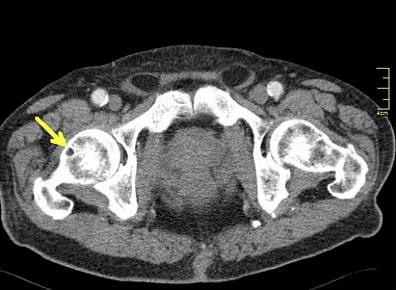

Here, this slightly older article mirrors a discussion we had on a recent podcast. We discussed the need for balance in the hip. More so, that focusing only on the glutes and hip extension can get one into trouble. One needs to also consider hip flexion skill, endurance and strength. The glutes and the hip flexors are a team to help maintain hip stability, mobility, and centration of the opposing joint surfaces during roll and glide motions. This is some of Shirley Sahrman's work, and others of course. When these component parts are not in harmony, and a loading force potentiates the femoral head towards the anterior labrum, it is the job of the glutes and hip flexors, to name two of the big players, to centrate that femoral head and keep it from impinging, and applying a forward load especially when this occurs during end motion loading into hip flexion and extension. I came across an article a while back that suggested these anterior directed movement risks are greater when the limb is loaded from being externally rotated, such as when making a strong power move or "cut" off the stance leg into the contralateral direction (we are looking for that source).

"Abnormal or excessive force on the anterior hip joint may cause anterior hip pain, subtle hip instability and a tear of the acetabular labrum.

We found that decreased force contribution from the gluteal muscles during hip extension and the iliopsoas muscle during hip flexion resulted in an increase in the anterior hip joint force. The anterior hip joint force was greater when the hip was in extension than when the hip was in flexion."